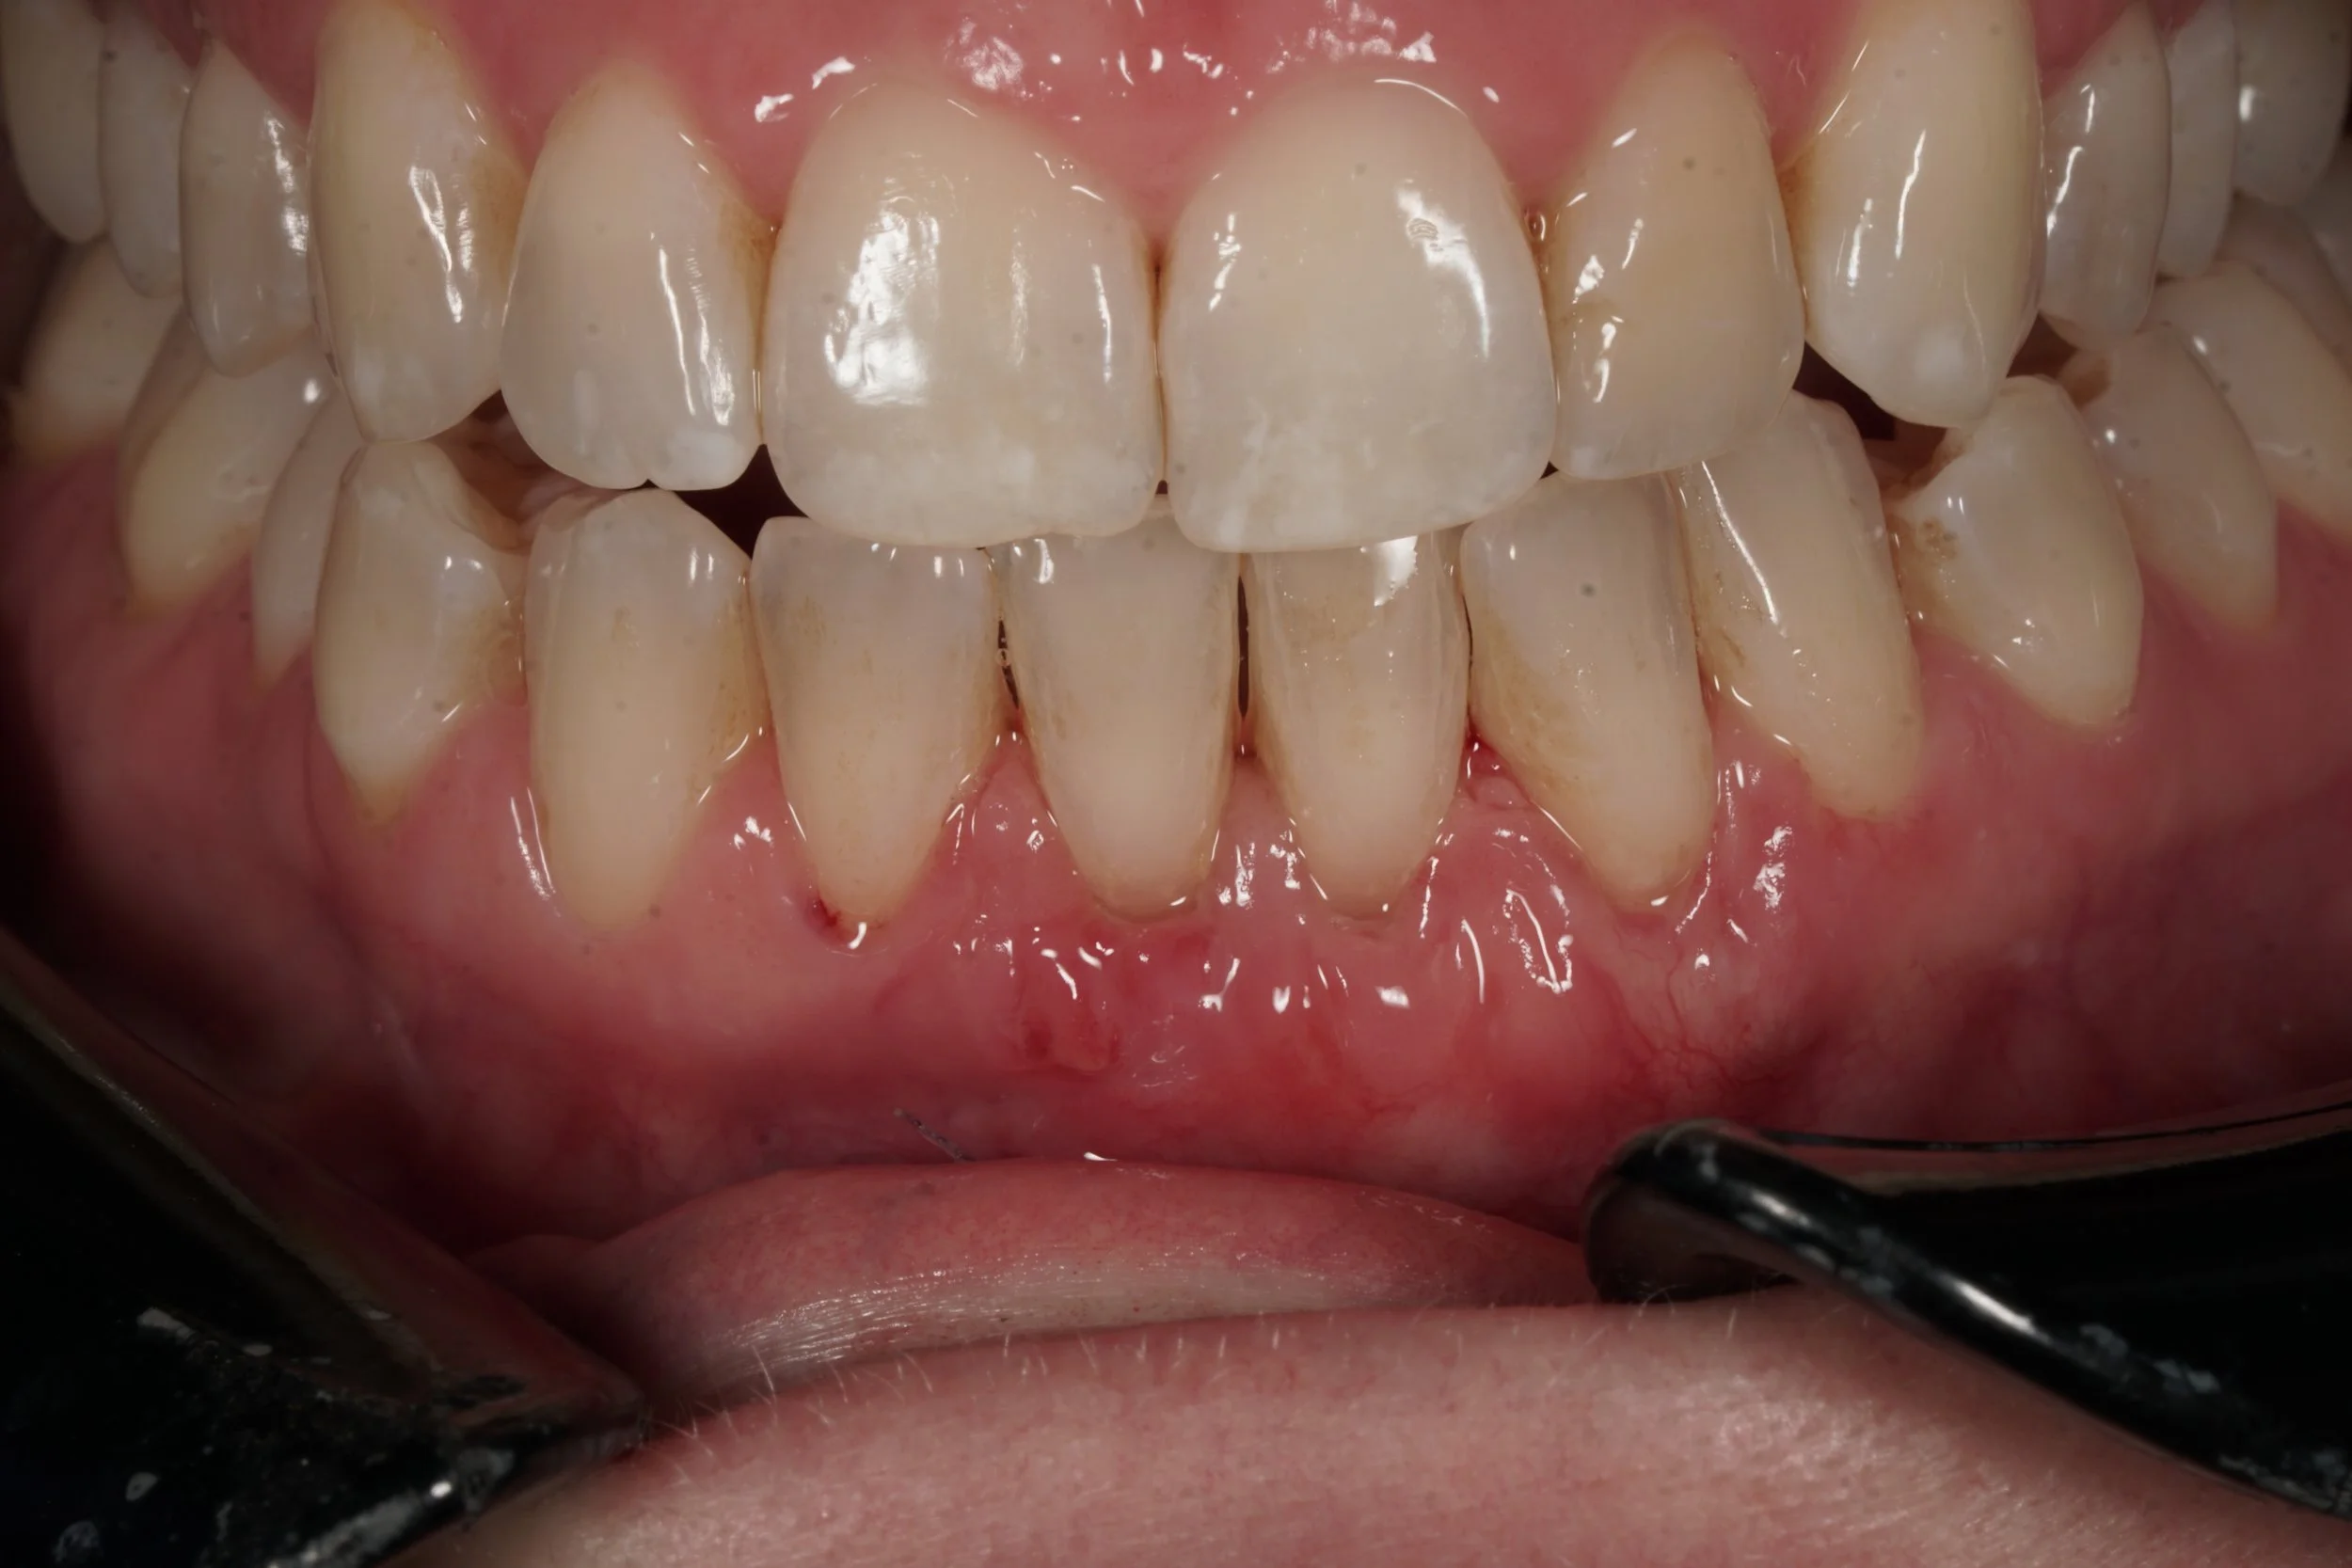

2 weeks after minimally invasive tunnel approach for gum grafting, connective tissue graft, showing thick and healthy newly formed gums successfully treated recessions